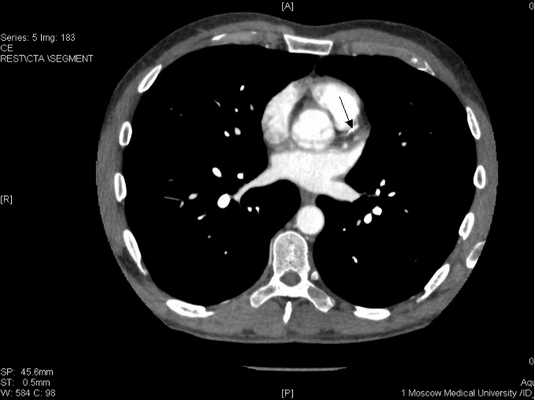

Поскольку от предложенной коронароангиографии пациент вновь отказался, была проведена мультиспиральная компьютерная томография коронарных артерий с контрастированием, которая продемонстрировала протяженный стеноз передней межжелудочковой артерии и окклюзию правой коронарной артерии

Рисунок 11. Стенозирующий атеросклероз коронарных артерий у больного К., 53 лет.

ПМЖВ в проксимальном сегменте имеет кальцинированную протяженную бляшку со стенозированием 50-75% (Указано стрелкой

ПКА в проксимальном сегменте окклюзирована (указано стрелкой), дистальный отдел и ЗМЖВ заполняются контрастным веществом.